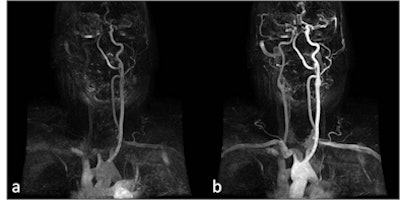

| Patient with transient ischemic attack. A: CT angiography depicted a large plaque involving the internal carotid artery characterized by a proximal calcified component and a distal fibrolipidic portion (arrows); first-pass MRI (B) identified a small and deep ulceration of the plaque surface that was partially hidden by calcifications in CT (arrow). C: Volume-rendered reconstruction. (Provided by Prof. Carlo Catalano and Dr. Beatrice Cavallo Marincola) |